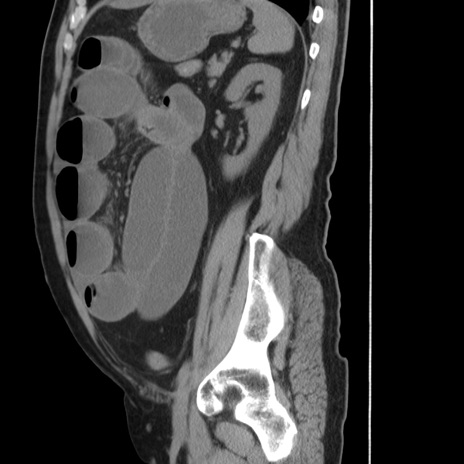

症例20(矢状断像)

【症例】 60歳代男性

【主訴】 腹部膨満、嘔吐

【現病歴】5日前頃より倦怠感を認め食事量減少し4日前の朝嘔吐、食事摂取困難となった。 3日前近医受診し点滴施行され整腸剤などを処方された。 当日他院を受診し、腹部膨満著明、炎症反応の上昇(CRP10.8、WBC11200)あり、紹介受診となる。

【身体所見】 意識JCS1 受け答えがはっきりしないBP 111/57mHg、 P 67bpm、、BT35.2°C、SpO2 97%(RA)、 腹部:膨隆、打診で鼓音あり、全体的に圧痛有り、腸蠕動音(-)、反跳痛ははっきりせず。

【データ】WBC 11400、CRP 14.20

横断像